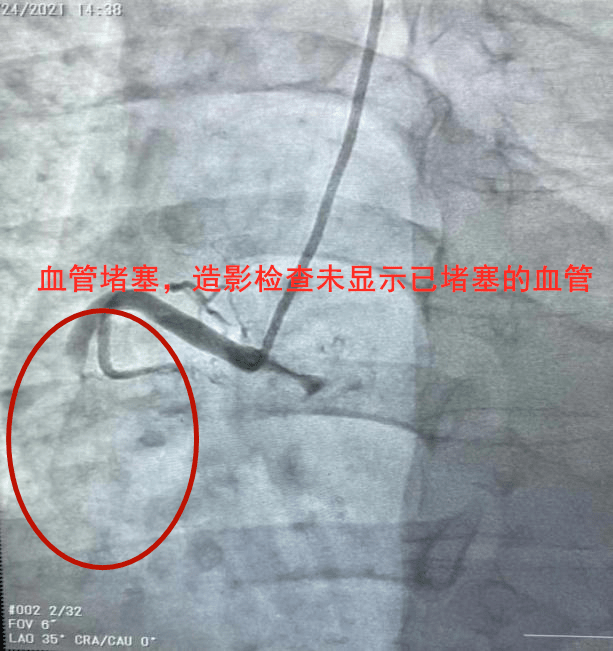

血管造影的副作用主要包括以下几点造影剂肾病当造影剂用量过大,或者病人本身肾功能不佳时,造影剂可能对肾脏造成损害,引发造影剂肾病血管及穿刺部位相关副作用局部出血在血管入路上,穿刺的部位可能出现局部出血血管损伤在血管走行区域进行操作时,如进钢丝或导管时,可能对血管壁造成损伤。

脑血管造影的副作用主要包括以下几点X线辐射脑血管造影需要使用X线进行成像,因此患者会接受一定量的X线辐射穿刺动脉相关副作用穿刺动脉时可能会出现大腿根部的血管夹层血肿血管闭塞等并发症动静脉瘘或下肢静脉血栓也是可能的副作用造影剂相关副作用使用造影剂时,患者可能会出现头痛发热等。